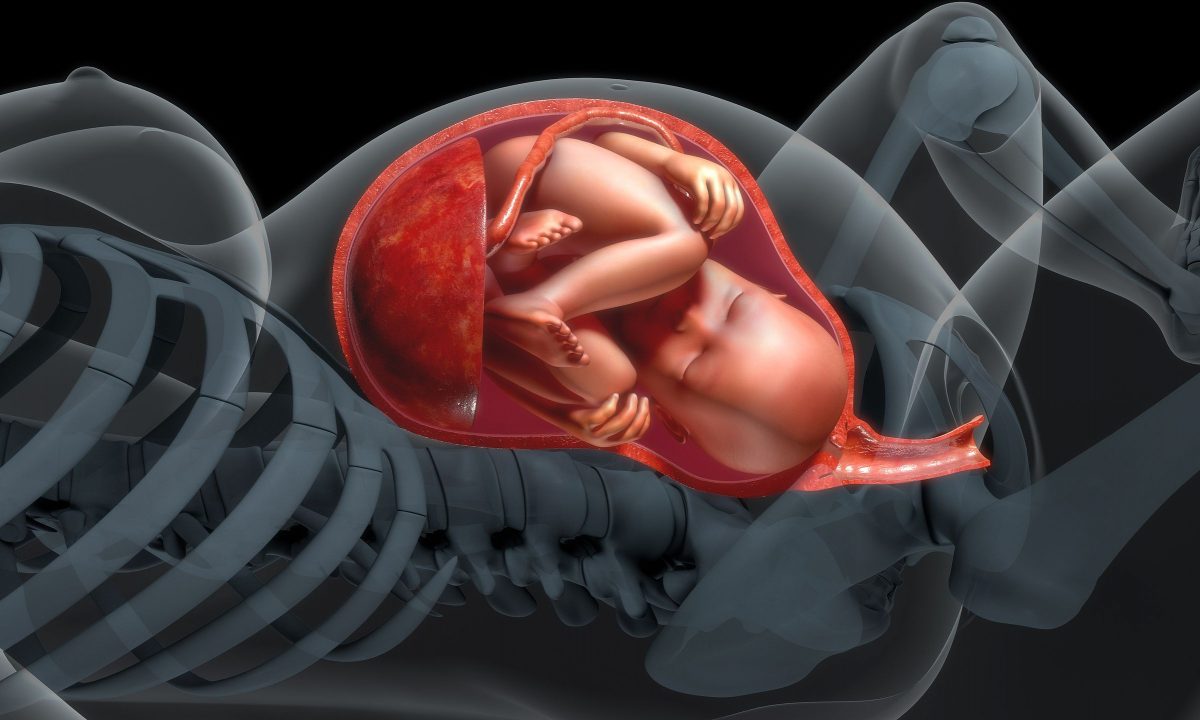

Ανάπτυξη εμβρύου: Το τρίτο τρίμηνο

Στο 3ο τρίμηνο το έμβρυο αναπτύσεται, παίρνει βάρος και ετοιμάζεται για τον τοκετό.

Η ανάπτυξη του εμβρύου συνεχίζεται στο τρίτο τρίμηνο της εγκυμοσύνης. Κατά τις τελευταίες αυτές εβδομάδες, τα μωρά παίρνουν περισσότερο βάρος και προετοιμάζονται για τον τοκετό.

Το τέλος της εγκυμοσύνης σου πλησιάζει! Μέχρι τώρα, είναι πιθανό να ανυπομονείς να γνωρίσεις το μωρό σου από κοντά. Όμως, εξακολουθούν να συμβαίνουν πολλές αλλαγές στο μωρό —το οποίο αποκαλείται έμβρυο— κατά τις τελευταίες εβδομάδες της κύησης. Χρησιμοποίησε αυτές τις πληροφορίες για να παρακολουθείς τι συμβαίνει εβδομάδα με την εβδομάδα στο τρίτο τρίμηνο.